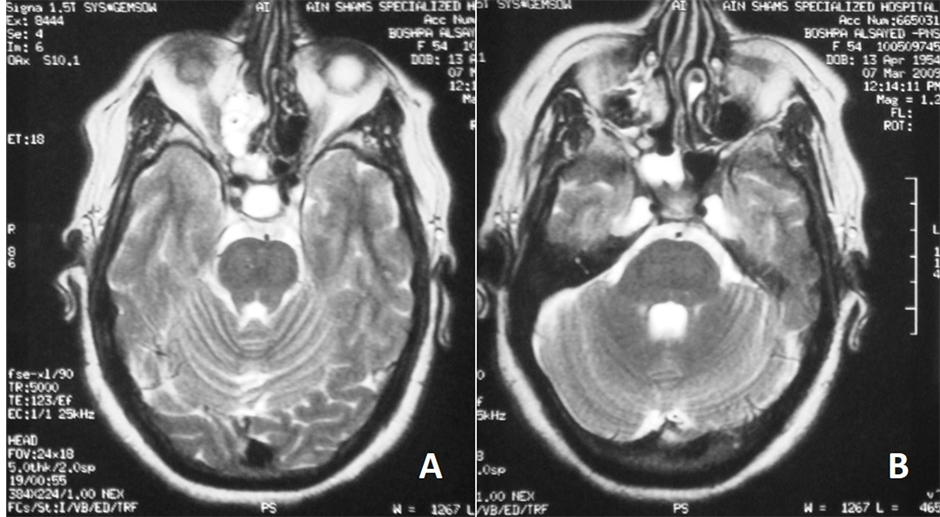

The radiological data suspicious of increased intracranial pressure were looked for in CT scan and MRI. All patients had empty sella syndrome (100%) whether partial or complete (Figure 3). Ten patients had slit-like ventricles and tight subarachnoid spaces, while only 5 patients had tortuous optic nerve (Figure 4).

Figure 3. Axial T2 weighted MRI of paranasal sinuses showing (a) empty sella syndrome; bilaterally distended Meckel’s cave (b). CSF leak is seen in the right ethmoid air cells and nasal cavity (a) & (b).